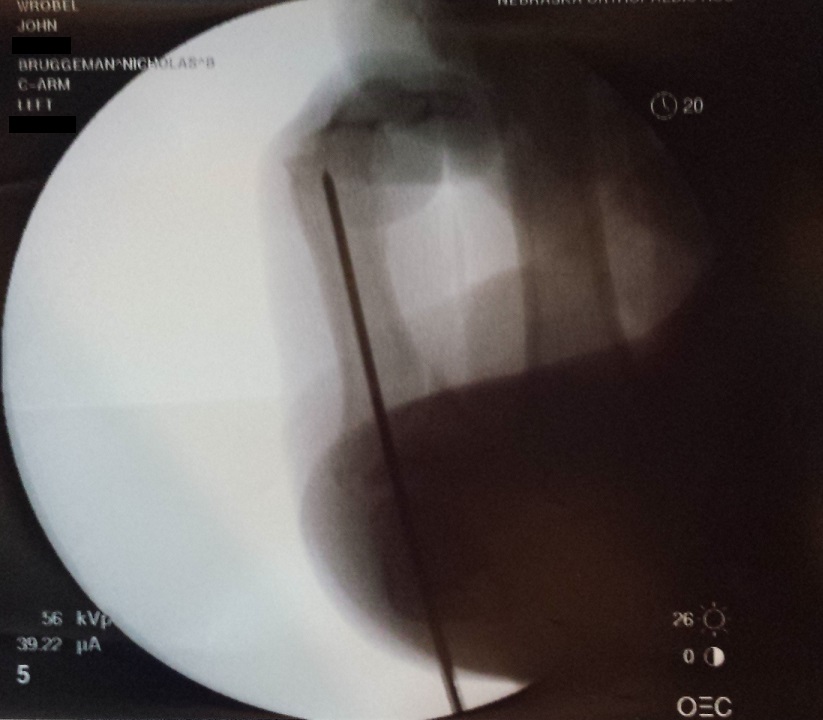

Thankfully I have insurance. But a trip to the emergency room followed up with surgery to put a pin in my finger is certainly going to go a long ways towards achieving the maximum out of pocket limit of my high deductible health plan. All things considered though, I was lucky that it wasn’t more serious. Just a broken pinky finger and some road rash.